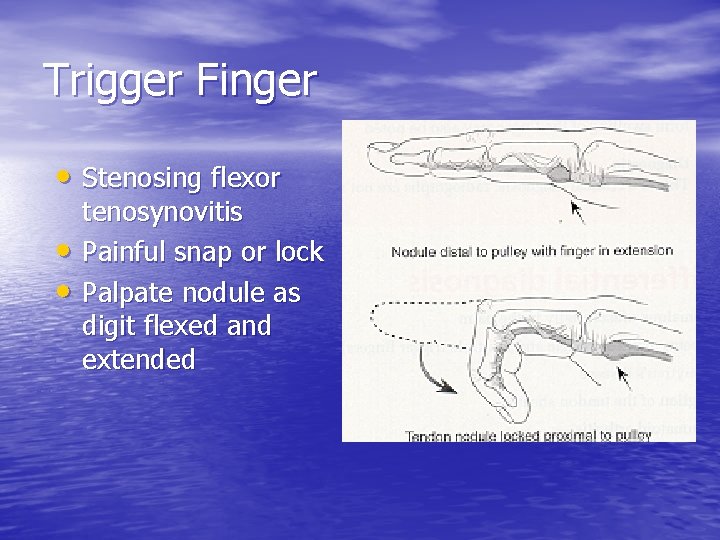

Trigger Finger • Stenosing flexor • • tenosynovitis Painful snap or lock Palpate nodule as digit flexed and extended